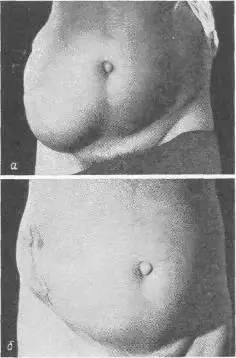

Больной С, 62 лет, в апреле I960 г. перенес операцию по поводу флегмонозного аппендицита, завершенную тампонадой и дренированием брюшной полости (рис. 106, а, б). Послеоперационное течение осложнилось обширным нагноением, пневмонией. Рана закрылась спустя 6 недель. Через полгода появилось большое выпячивание в области операции. По поводу послеоперационной грыжи был оперирован, но спустя короткое время наступил рецидив. Выпячивание увеличивалось. Больной носит бандаж. В июне 1962 г. грыжа стала невправимой, начали беспокоить боли.

Рис. 106. а — вентральная грыжа после аппендэктомии у мужчины 62 лет; б — тот же больной после пластической операции.

Объективно: больной — тучный мужчина, высокого роста, вес 102 кг. Послеоперационный рубец длиной 20 см. Грыжевое выпячивание размером 20 Xl5 Xl см, вправляется с трудом. На рентгеноскопии в грыжевом мешке обнаружены петли тонкой и сигмовидной кишок. Операция под эфирно-кислородным наркозом. Из рубцово-измененных тканей с трудом выделены края грыжевого дефекта (16x10 см). Петля тонкой кишки сращена со стенкой грыжевого мешка. Спайки разделены. Грыжевой мешок ушит (рис. 107 а). Произведена пластика путем подшивания двух листков капроновой сетки к краям дефекта передней брюшной стенки (рис. 107, б, в, г) [32]. Над верхним листком капрона зашита подкожная клетчатка. Рана зажила первичным натяжением, однако к 20-му дню на месте небольшой серомы образовался инфильтрат и усилилось выделение серозной жидкости из углов раны. Спустя 6 недель после операции больной был выписан для амбулаторного лечения. Через месяц поступил повторно по поводу продолжающегося выделения серозно-слизистой жидкости. Лишь спустя 4 месяца после операции отделяемое прекратилось после повторного извлечения нитей капрона из образовавшихся свищей. Рецидива грыжи нет. Закрытие прочное.